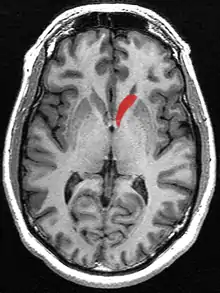

Caudate nucleus

Caudate nucleus (in red) shown within the brain

This is a transverse view of the caudate nucleus from a structural MR image.

Transverse view of the caudate nucleus from a structural MR image